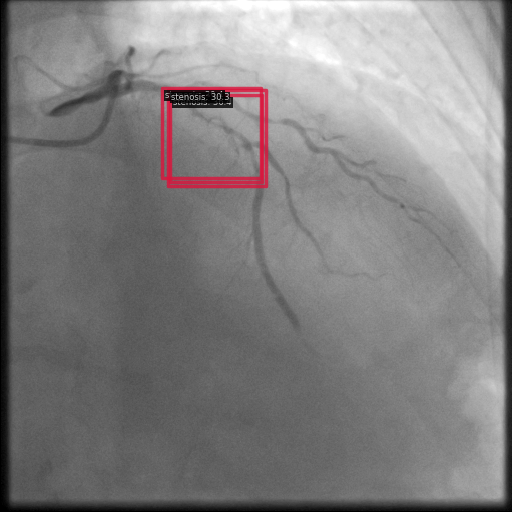

Figure 1 shows sample images from the ARCADE dataset with annotations for stenosis detection. The annotations highlight regions of arterial narrowing, providing ground truth data for training and evaluating object detection models.

To further assess the detection performance, qualitative results for three test images are presented in Figure 2. The first column shows the original images with ground truth annotations. The second, third, and fourth columns depict detections from DINO-DETR, Grounding DINO, and YOLO, respectively.

(a) Original (b) DINO-DETR (c) Grounding DINO (d) YOLO

The qualitative comparison in Figure 2 reinforces the trends observed in the quantitative evaluation. DINO-DETR produced fewer detections, occasionally missing relevant stenotic regions, consistent with its conservative detection strategy aimed at minimizing false positives [6]. Grounding DINO, although capable of identifying more regions, sometimes resulted in cluttered predictions due to over-detections [7]. YOLO provided a reasonable trade-off by effectively capturing anatomical structures while maintaining relatively high confidence scores and clear visualizations [5].